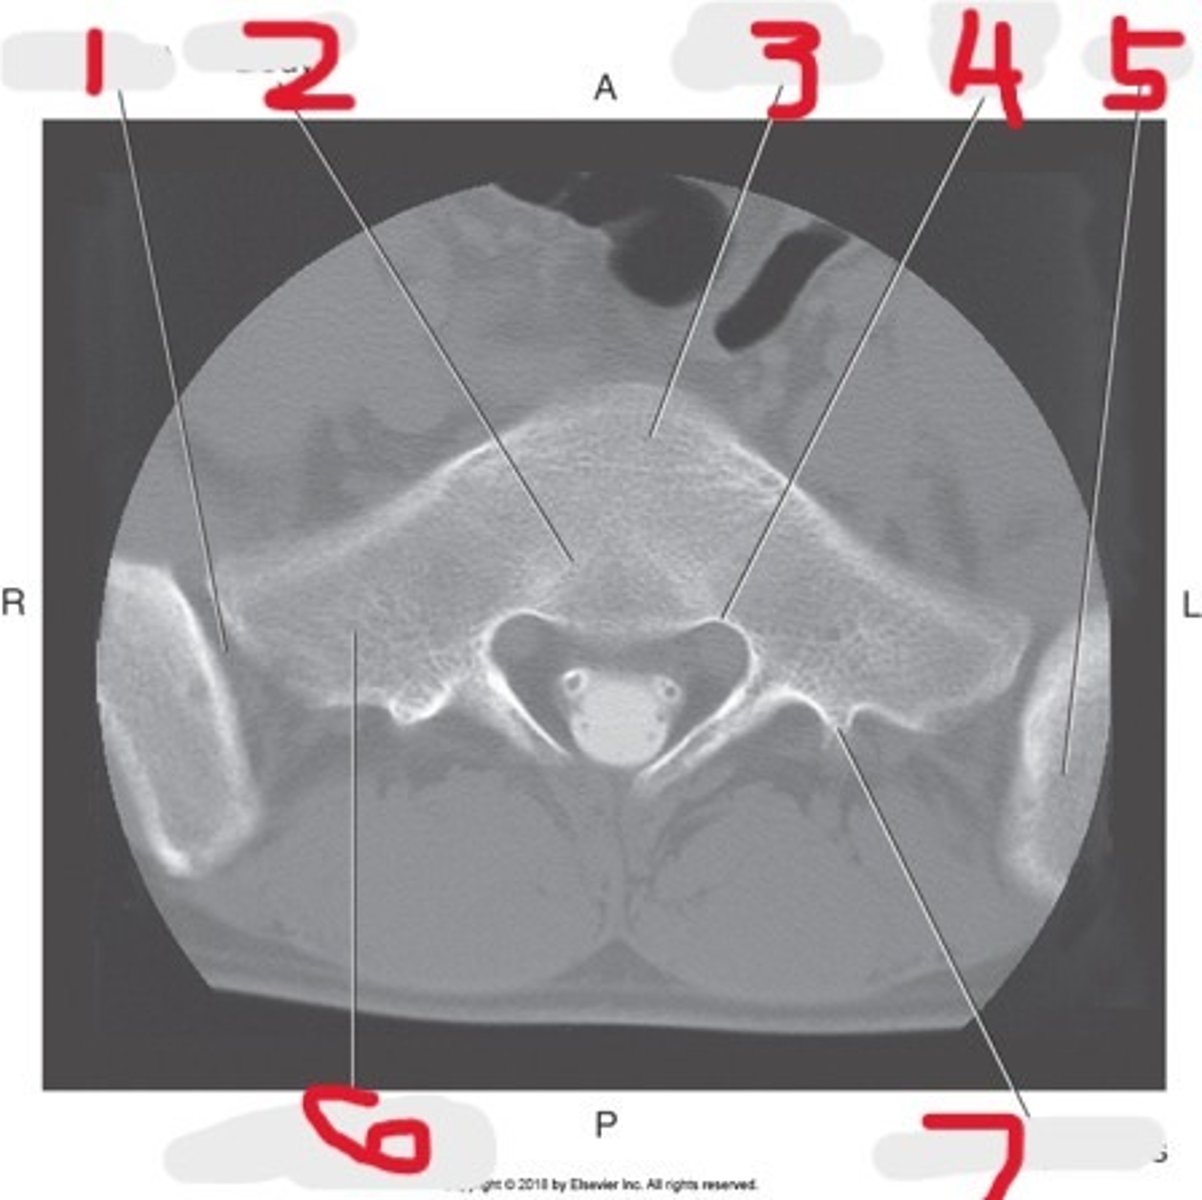

1) SI joint

2) Body

3) Sacral promontory

4) Sacral canal

5) Ilium

6) Lateral mass

7) Articular process

Name all numbered structures

1) Ala of ilium

2) SI joint

3) Sacral promontory

4) Lateral mass of Sacrum

5) Sacrum

Name all numbered structures

1) Ala of ilium

2) SI joint

3) Sacral promontory

4) Lateral mass of sacrum

5) Sacrum

6) Ilium

Name all numbered structures

1) Lateral mass

2) Sacral promontory

3) Ilium

4) Sacral foramina

5) Body

6) Sacrum

7) SI joint

Name all numbered structures